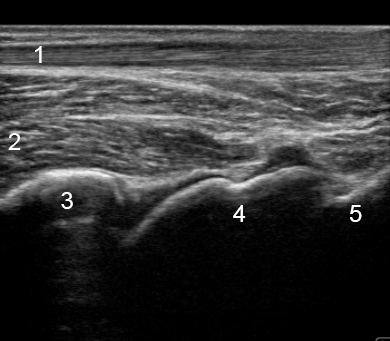

踝部后胫距隐窝

跟腱

拇长屈肌 (FHL)

胫骨

距骨

跟骨